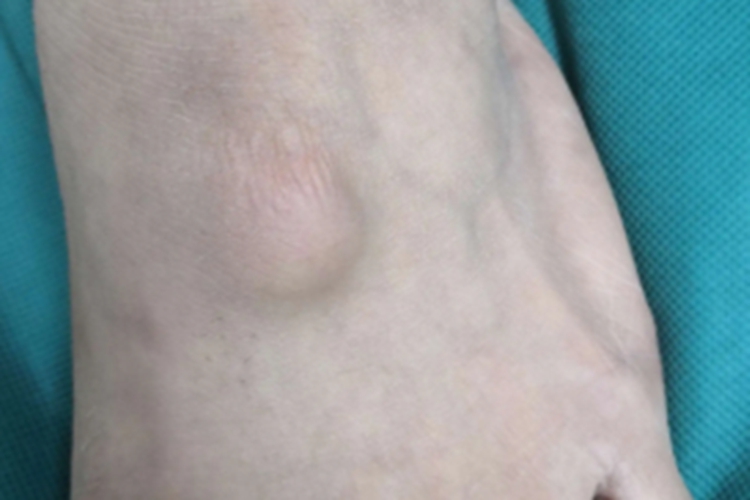

腱鞘囊肿可出现在部分患者的脚背,表现为圆形肿物,为鹌鹑蛋大小,高于皮肤表面,看着像是大包。损害轻微发红、肿胀,不与皮肤粘连,扪之如硬橡皮样实质性感觉,与周围正常组织边界明显,患者在行走摩擦此处时可感到疼痛。用粗针头穿刺可抽出透明胶冻状物。